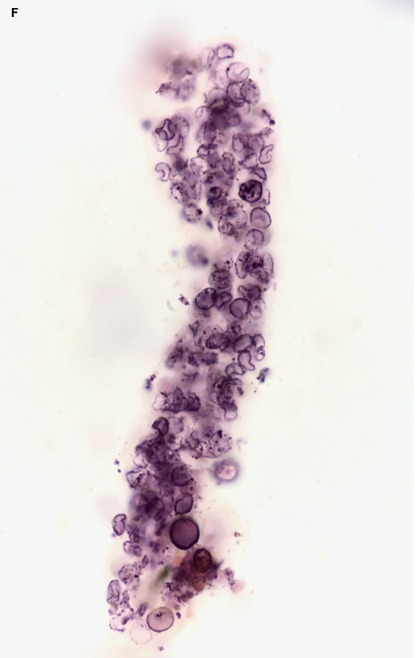

Figure 1. RBC Casts A. BFI, SM stain; B. BFI, unstained C. Phase contrast, unstained D. BFI, with embedded renal tubular epithelial cells (RBC: red blood cell; BFI: brightfield illumination; SM: Sternheimer-Malbin)

RBC casts form when RBCs which have entered the tubular lumen are trapped within solidified Tamm-Horsfall protein matrix. These casts may have a variable appearance with some containing only a few RBCs and others so densely packed that individual cells and protein matrix are difficult to see without higher magnification.

Red blood cell casts can be an elusive finding and require a diligent search, often using different illumination modalities and magnifications. What appears on low power to be a dense granular cast may upon review under higher magnification actually contain RBCs! RBC casts are fragile and easily degenerate. They are subject to fragmentation or disruption at higher centrifuge speed and may disintegrate if the sample is left too long before examination.